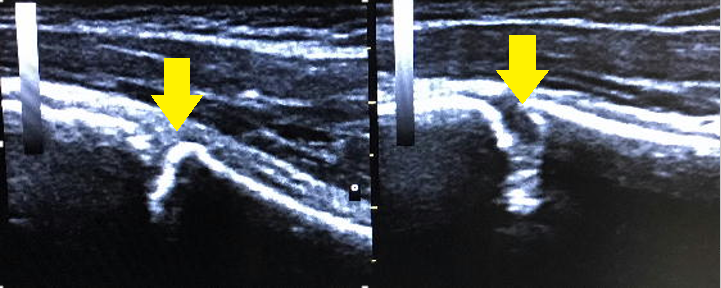

※画像:左が健側、右が患側です。

【症例2:上腕骨近医骨端線離開(リトルリーガーズ・ショルダー)】

中学1年生ピッチャー。ボールを投げても力が入りにくくなっている感覚がする。

「腕が振れない」という主訴で来院。

骨端線の開きが著明である。